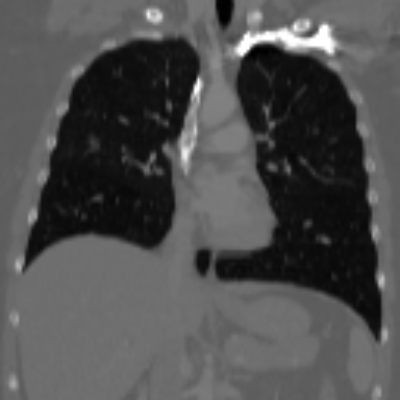

| Axial | Coronal | Sagittal | |

| X2CTGAN | ![]() |

![]() |

|

| DX2CT | ![]() |

| Ground-truth | ![]() |

Figure 3 and Table I(a) using biplanar X-rays show that proposed DX2CT can outperform three existing SOTA methods. Figure 3 shows that DX2CT can provide more accurate overall shapes and details compared to the existing methods. The quality of reconstructed CT slices in the axial plane is less satisfactory than those in the other planes. The reason is that the axial plane is perpendicular to the planes of biplanar X-rays so there exists less spatial (i.e., depth) information in the axial plane. Without using the perceptual loss [33], proposed DX2CT gave comparable LPIPS results with PerX2CTs using [33] in training. Compare their LPIPS results in Table I(a).